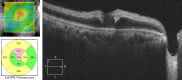

Retinal vascular events may occur as rare complications of glaucoma procedures due to various factors, including exacerbation of ischemia in patients with pre-existing vascular comorbidities, toxic effect of mitomycin-C, and decompression retinopathy. We present the case of a 47-year-old hypertensive male who underwent trabeculectomy for advanced glaucoma in his right eye. At 3 weeks postoperatively, he presented with a drop in visual acuity to light perception with a spike in intraocular pressure. On examination, there was increased bleb vascularity as well as rubeosis. Fundoscopy revealed findings consistent with both central retinal artery occlusion and central retinal vein occlusion. Combined central retinal artery and vein occlusion is a rare retinal vascular condition. Neovascular glaucoma can occur as a sequelae of the ischemic process in the retina. Despite treatment, there is a poor visual prognosis, with the affected eye usually becoming blind from optic atrophy and neovascularization.